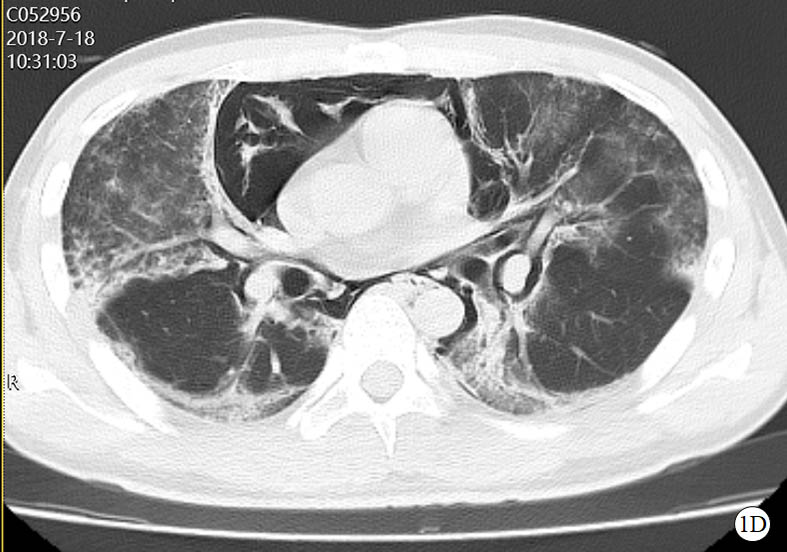

图 1 患者口服百草枯后胸部CT影像学变化

2018-07-18 CT图